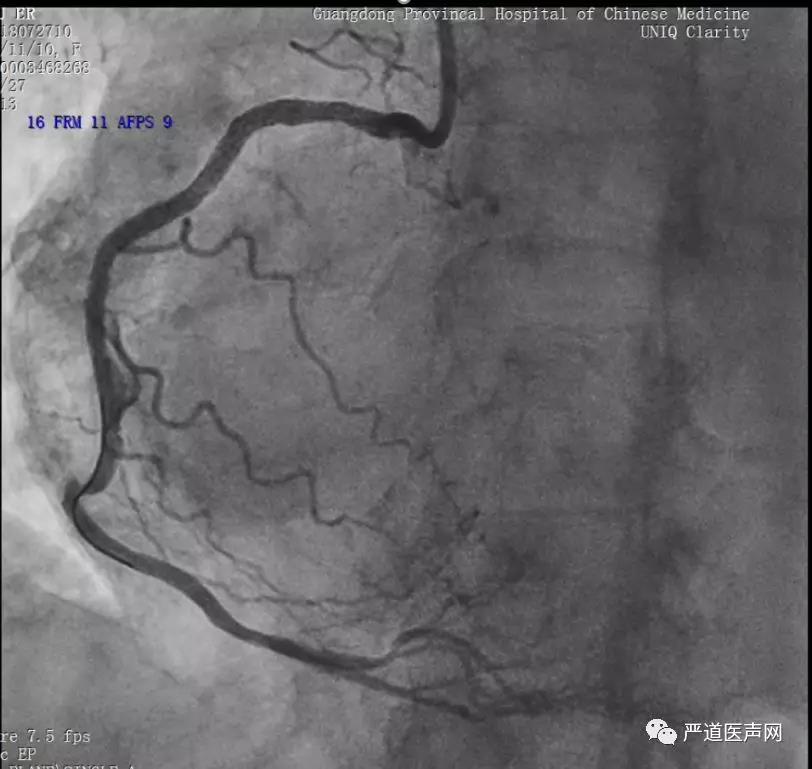

首先何志凌教授带来了一例迂曲RCA病变的报告。患者女性,74岁,主诉胸闷、胸痛1月,既往高血压、结肠息肉切除、萎缩性胃炎。实验室检查:BNP1237pg/ml。UCG示左心室稍大,主动脉瓣、二尖瓣中度返流。行冠脉造影示RCA迂曲伴多发狭窄。诊断为冠心病。

手术策略为先处理近端狭窄,改善血流量后再处理远端病变。先后用2.0×15mm和2.5×15mm球囊扩张,在Guidezilla导管的支撑下,远端植入2.5×24mmExcrossal(心跃)支架,近端植入2.75×33mm Excrossal(心跃)支架,术后造影如下图。随访未发生任何不良事件。